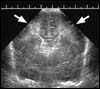

Alors que les cardiologues, les angéiologues, les gynécologues, ou les gastro-entérologues disposent d'un accès direct aux moyens d'imagerie les plus modernes, les rhumatologues restent les parents pauvres des services hospitaliers. Pourtant, la rhumatologie est une spécialité en pleine extension, avec de nouveaux traitements d'efficacité notable, dont les résultats sont d'autant plus spectaculaires que la maladie est traitée de manière intense et précoce. Or, la mise en œuvre d'un tel traitement ne peut se faire qu'au vu d'images permettant de faire le bilan, puis de suivre l'évolution d'un certain nombre de maladies inflammatoires graves, telle la polyarthrite rhumatoïde.